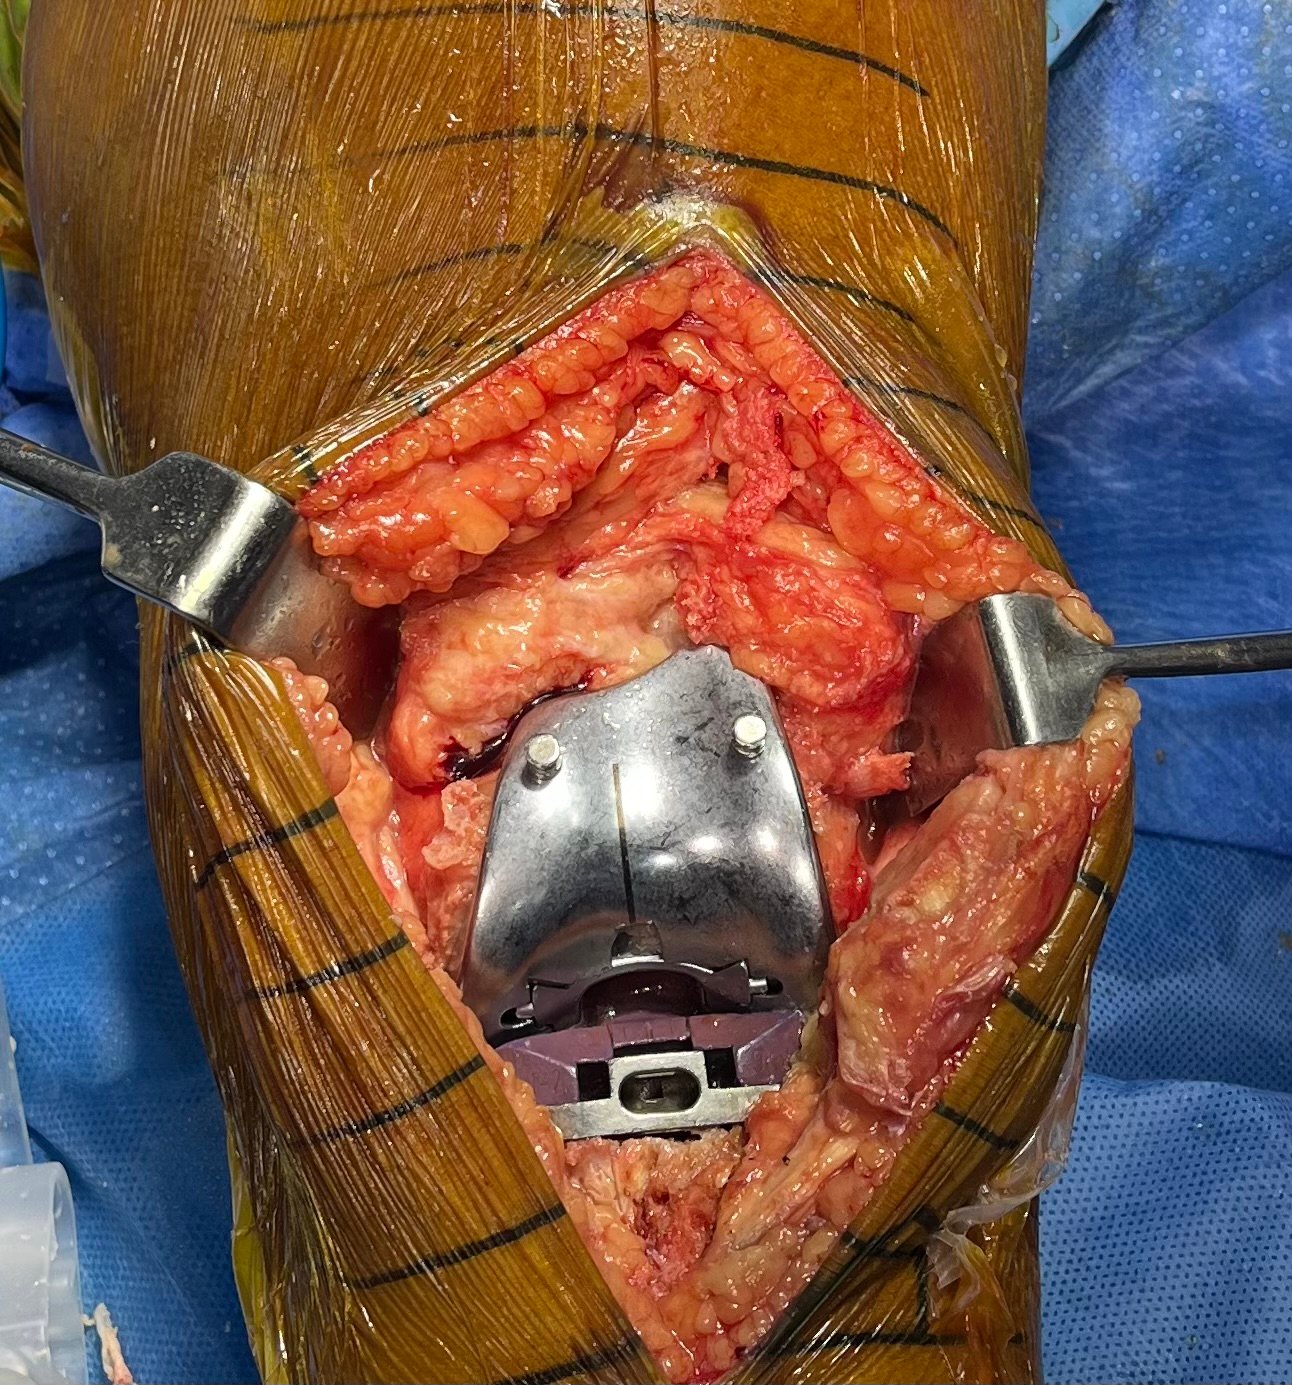

Rheumatoid Arthritis with Synovial Hypertrophy

Intra-Op (Photos)

Final Component

DFC & Tibial Cut